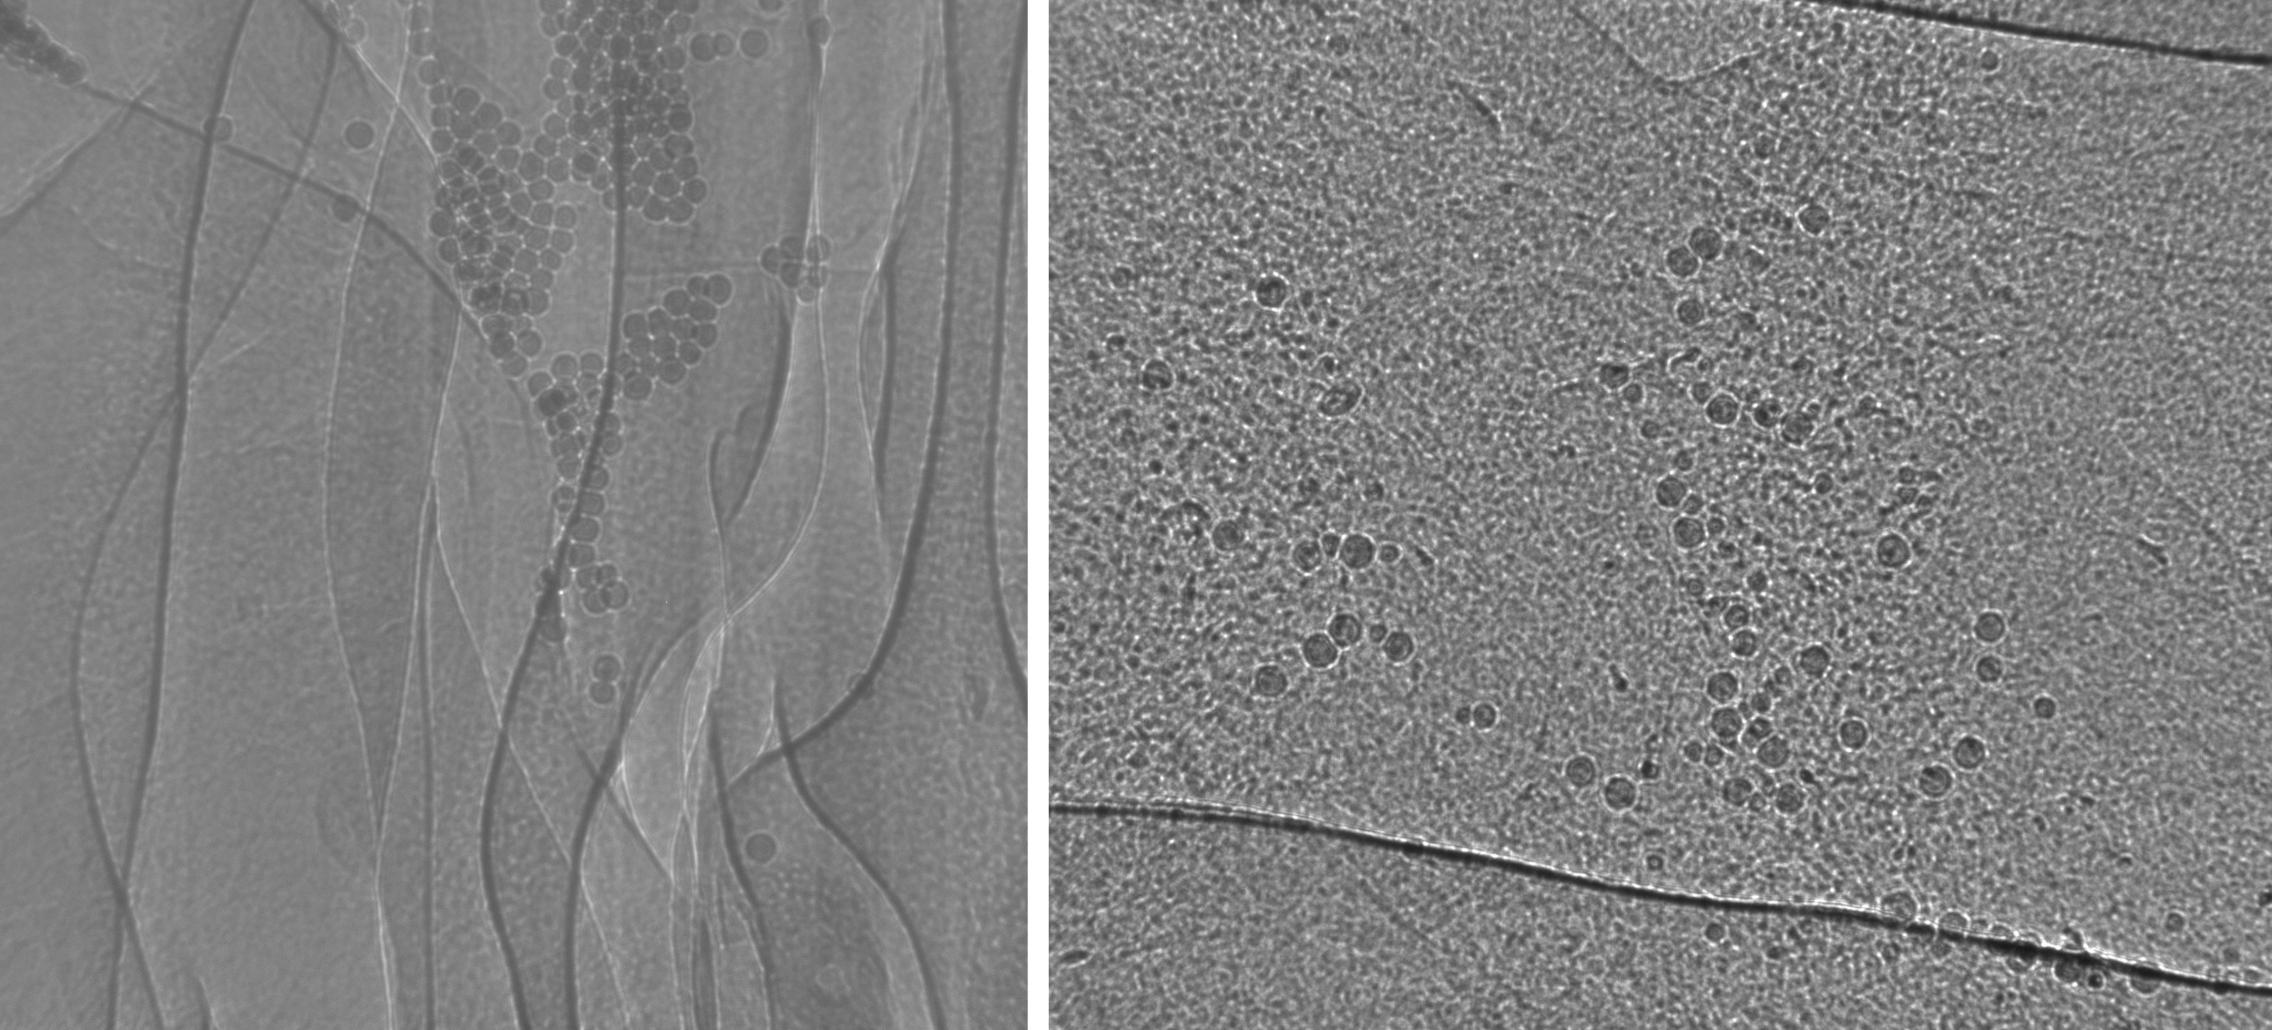

In 2013B SPring-8 studies (left) we have demonstrated the use of glass microspheres as suitable particles for tracking MCT in the nasal airway of CF and normal mice. In 2014A studies (right) we extended this method to the trachea of normal mice. The particles are moved by beating cilia on the airway surface, allowing us to assess the effectiveness of this biological process, and how it changes with treatment. Images ~1.2mm high.

In 2014A studies at SPring-8 Synchrotron in Japan we examined the MCT behaviour of real environmental lead dust (< 50 µm particle size) collected from around Port Pirie. Image is ~1.2 mm high. Here dust can be seen preferentially moving toward the dorsal surface of the trachea. Dust motion is only visible in the moving images due to the phenomenon known as "motion popout"

In 2015-1 studies at the Australian Synchrotron Imaging and Medical Beamline we examined the MCT behaviour of 100 µm particles in segments of excised sheep trachea. Image is ~14 mm high. These studies were performed with a future view to examining MCT in CF pig and CF ferret airways, to quantify the effect of pharmaceutical and genetic therapies in new CF animal models.